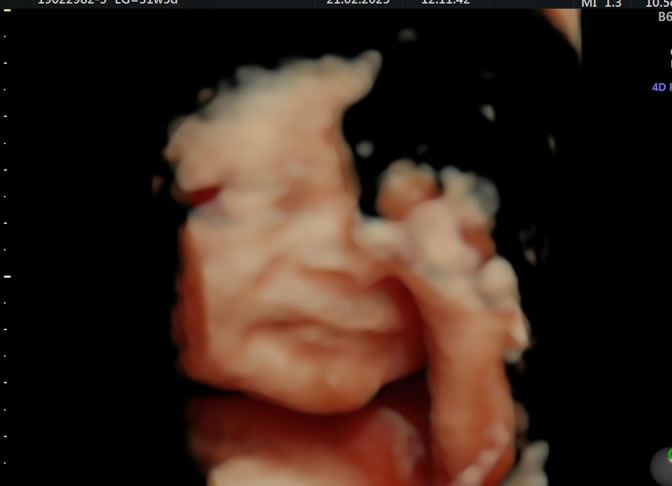

• Eco Doppler III Trimestre

Doppler Center